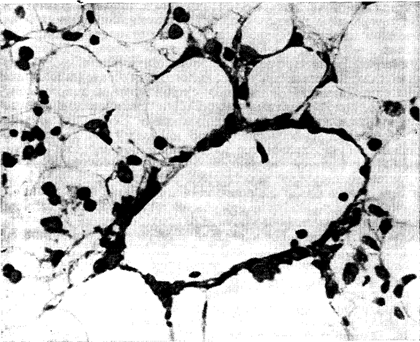

При алкогольном фиброзе печени переход заболевания в цирроз печени происходит без развития клинических или гистологических признаков гепатита. Больных беспокоят общая слабость, длительные боли в верхней половине живота, диспепсические нарушения. Активность АсАТ, АлАТ и •у-ГТП повышена в меньшей степени, чем при алкогольном гепатите. В пунктатах печени выявляют центральный и нередко портальный фиброз, а также перицеллюлярный фиброз, часто в сочетании с жировой дистрофией, но без воспалительных и некротических сдвигов (рис. 7).

Рис. 7. Центрально-дольковыи алкогольный фиброз печени. Микрофото. 16Х7. Окраска по Ван-Гизону.